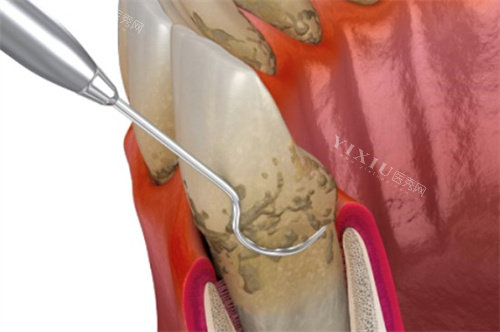

清除感染:清除根管内的感染物质,进行深度消毒。

根管充填:用合适的材料充填根管,切断感染源,消除根尖周炎症。